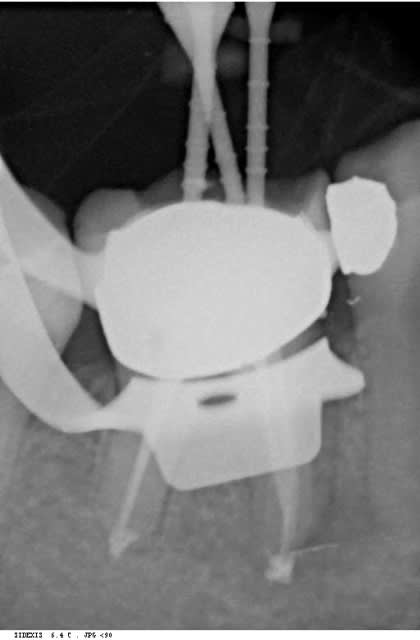

dans la même philosophie de connectique

Easyimplant mjxotp - Eugenol

Rvg easy briwxo - Eugenol